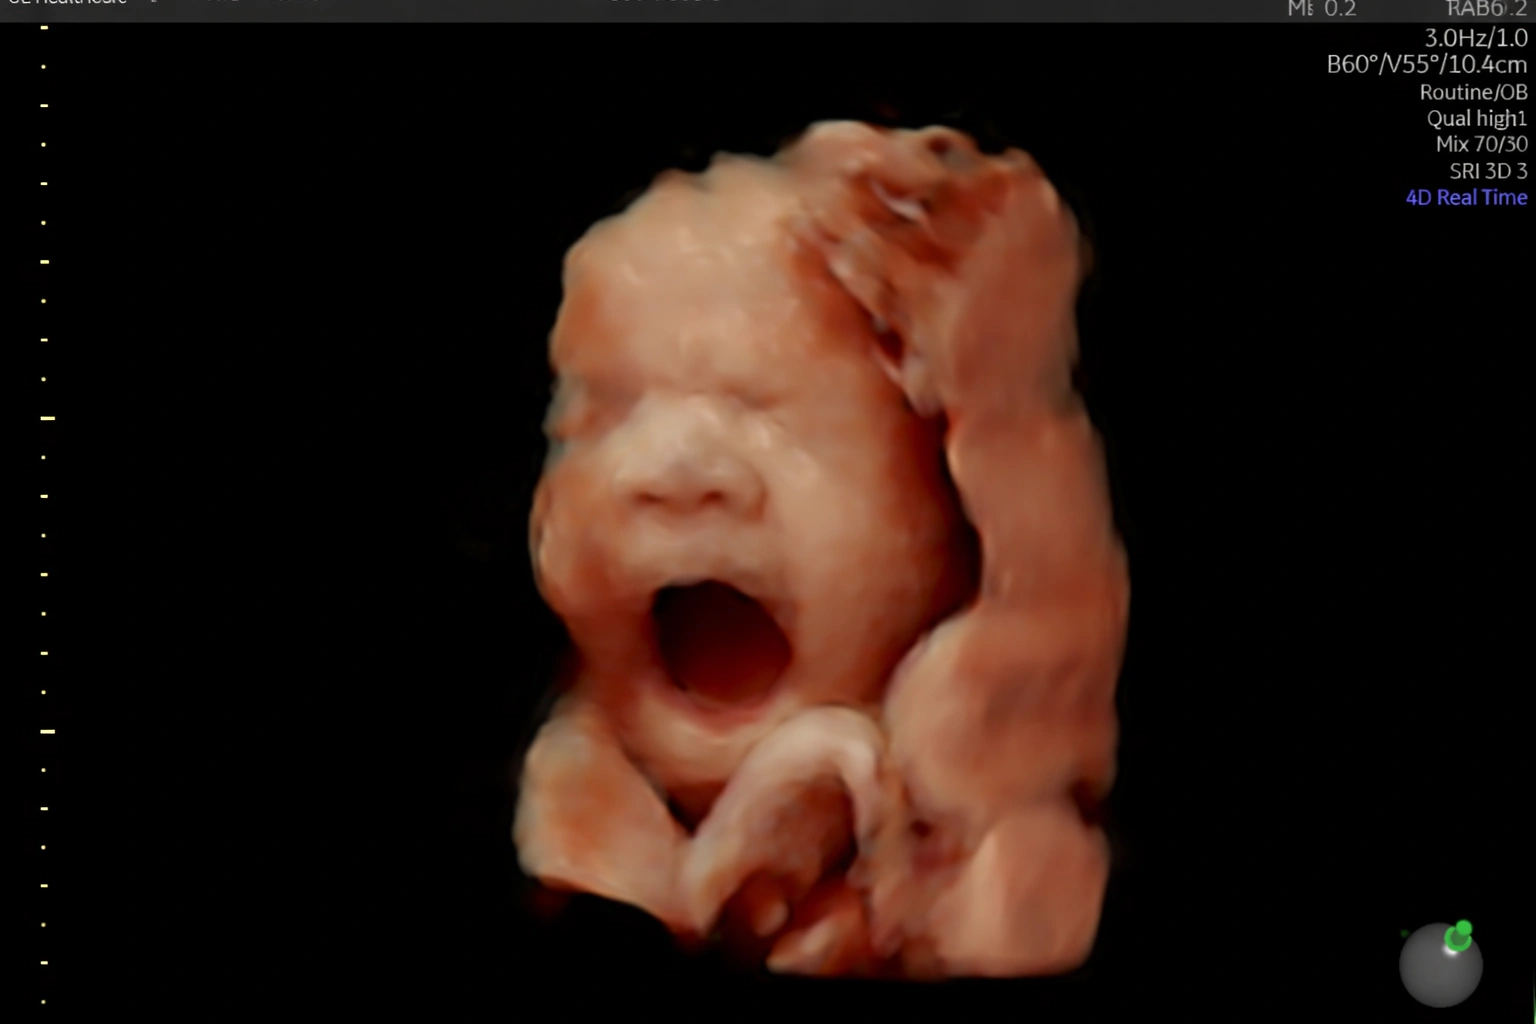

Acompanho detalhadamente toda a evolução do seu bebê ainda na sua barriga.

Realizo diversos tipos de ultrassonografia para garantir que seu bebê chegue ao mundo com saúde.

Através de exames precisos, conseguimos detectar quaisquer problemas antes mesmo do seu bebê nascer e corrigirmos para que ele venha com saúde.

Estou pronta para realizar diagnósticos precisos sobre como anda a saúde do seu bebê ainda ai dentro da sua barriga. Realizo toda e qualquer tipo de ultrassonografia obstetríca.